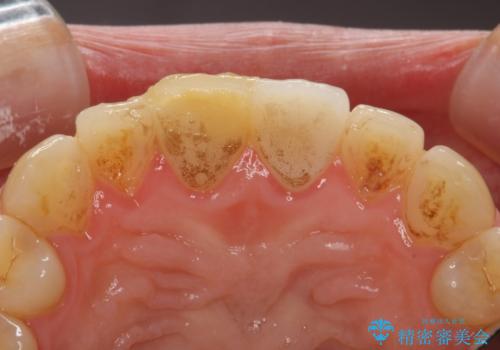

- 右上の前歯が折れたことを主訴に来院された患者様です。

歯が折れた部分は他院により応急処置で仮止めされていました。

欠けた範囲が大きかったため、セラミッククラウンによる補綴治療を行いました。